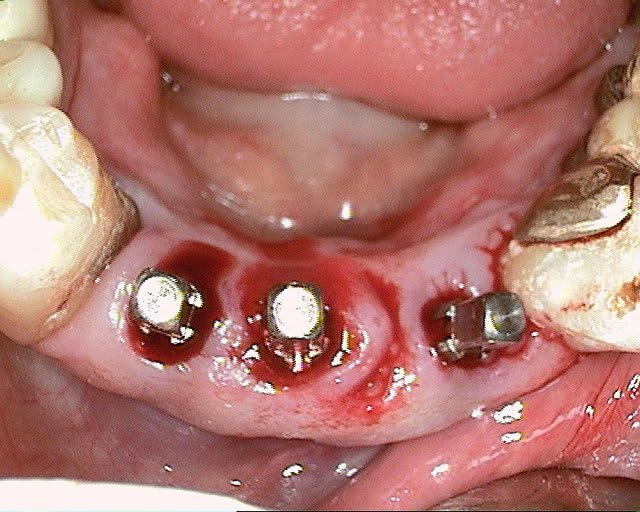

merci pour tes réponses, pour ma part (expérience avec plus de 600 implantation immédiate) je ne pense pas qu'il va y avoir une résorption, car pas de lambeau et tu n'as pas mis de trop grande pression sur l'os buccal.Un exemple ci dessous implantation ( 4 semaines après extraction) avec un 4.5 que (oui déjà mis dans un autre post).J'ai d'autres exemples similaires en extraction implantation immédiate mais avec des implants 3.5mm.Si l'espace entre l'implant et l'os buccal est plus grand que 1mm j'ajoute du collagène et de l'acide hyaluronique pour accélérer la régénération.

dernière radio à un an après cémentation de la couronne.

Ce qui est non négligeable est d'avoir une stabilité primaire d'un minimum de 35Ncm et pas plus de 70Ncm.

un cas récent os vestibulaire très fin.